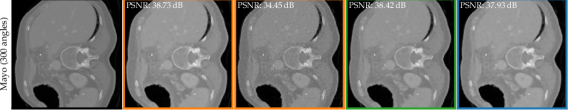

4.3 Mayo Clinic dataset [39]

To investigate a medical setting, we use 10 clinical CT images of the human abdomen released by Mayo Clinic [39] and study the behaviour of subspace optimisation in a medical image class. We reconstruct from a simulated fan-beam projection, with 300 angles and white noise with the noise scaling parameter , cf. (9). As a more ill-posed reference setting, we use 100 angles (comparable sparsity to the Walnut setting) and Gaussian noise with . For both tasks, we use the M parameter U-Net, as in Section 4.2, pre-trained on 32k ellipse samples. For the sparse setting (100 angles), we use a k dimensional subspace constructed from k checkpoints, but . For the more data-rich setting (300 angles), we use k, sampled from k checkpoints, and similarly, we sparsify it down to .

Fig. 6 shows example reconstructions using 100 and 300 angles. If stopped within a narrow max PSNR window, DIP and E-DIP can deliver reconstructions that better capture high-frequency details than Sub-DIP methods as one would expect. However, while the DIP and E-DIP reconstructions become noisy once they start to overfit, Sub-DIP methods do not exhibit any noise. We deem the increased robustness vs reduced flexibility trade-off provided by the Sub-DIP to be favourable, even in the well-determined setting.